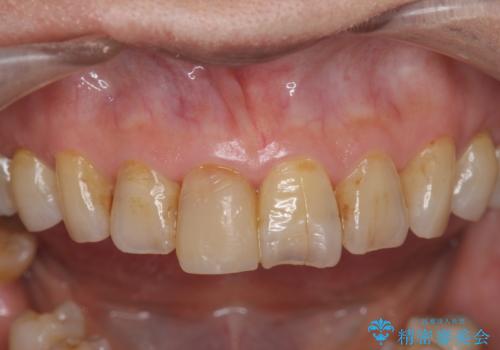

- 前歯を転倒で受傷し、審美性の回復を求めて来院されました。

近医で暫間的なコンポジットレジン修復が為されていましたが、色調に不満があるということでした。